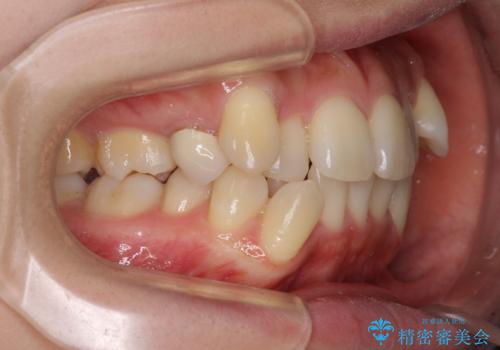

右側の上下は歯が重なり合って、内側に移動してしまうほどであり、それに伴って正中の位置が右側にずれている状態でした。

上下左右の第一小臼歯4本を抜歯して行うことになりますが、それだけでは咬み合わせの改善や正中位置の改善が困難であると判断されたため、アンカースクリューを用いた補助装置を併用することで、スムーズかつより良い仕上がりを目指すこととしました。